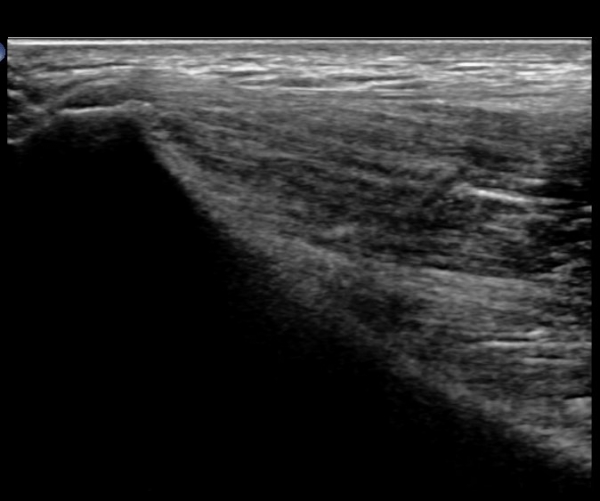

ÃÊÀ½ÆÄ°Ë»ç: °í°üÀý ¾ÕÂÊ Á¾´Ü¸é °Ë»ç¿¡¼­ °üÀý³¶ÀÌ µÎ²¨¿öÁö°í °æ¹ÌÇÑ °üÀý³» ºÎÁ¾À» º¸ÀÓ(»çÁø1, 2)

°í°üÀý À§, ¿ÜÃø¿¡¼­ ´ëÅðÁ÷±Ù Á¾´Ü¸é°Ë»ç»ó  ´ëÅðÁ÷±Ù °ðÀº ¼¶À¯(direct) ±â½ÃºÎ¿¡ ¹Ì¼¼ÇÑ

¼®È¸¼º º´º¯À» º¸À̳ª ÈûÁÙÀÇ Àú¿¡ÄÚ ºÎÁ¾Àº °üÂûµÇÁö ¾ÊÀ½.(»çÁø 3, 4)